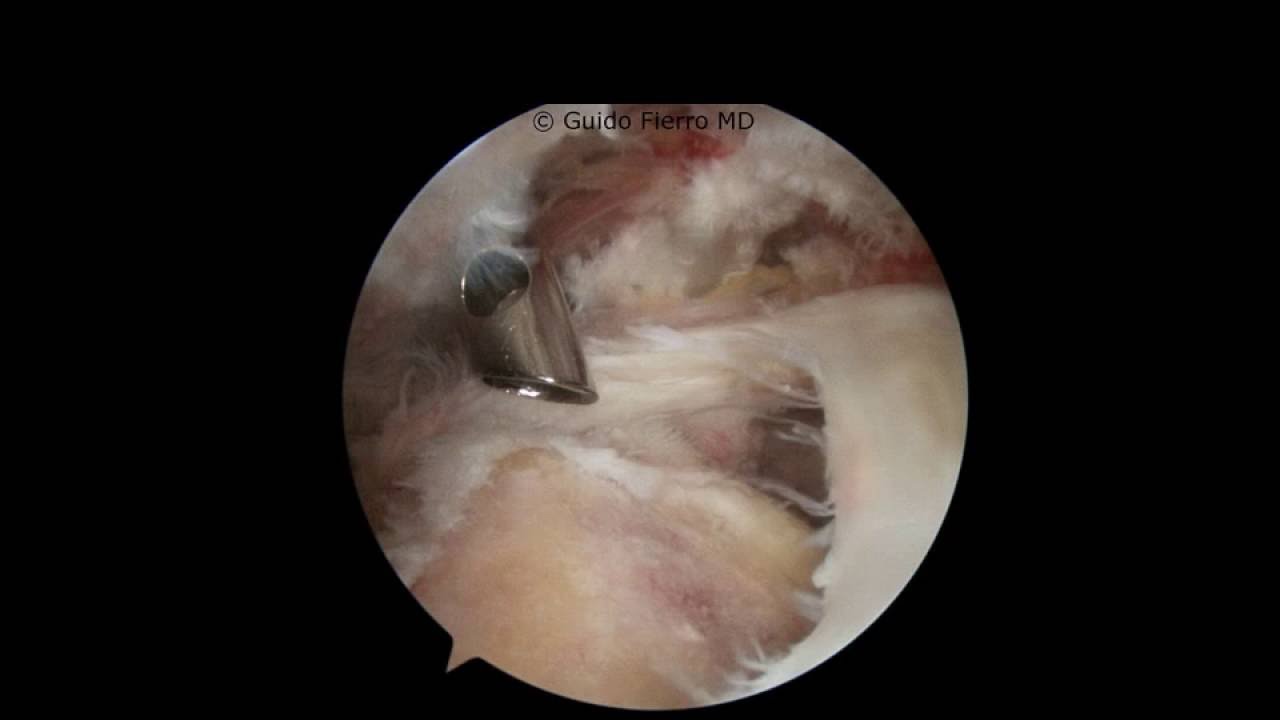

Artroscopia de hombro

¿Qué es artroscopia? La artroscopia es un procedimiento quirúrgico, en el cual el cirujano visualiza, examina, diagnostica y trata problemas en una articulación. Las articulaciones donde más frecuentemente se realiza este procedimiento son: rodilla, hombro y codo. La palabra artroscopia viene del griego “Arthro” que significa articulación y “Skopein” que significa mirar, es decir artroscopia significa mirar dentro de una articulación.